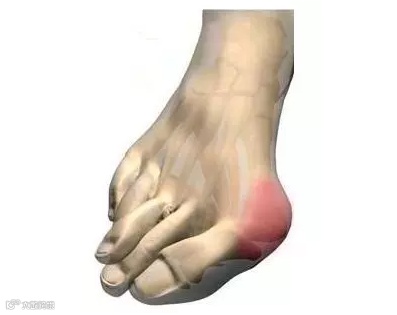

拇外翻是什么?

拇外翻,也被称为“大脚骨”或“拇趾外翻”,是指拇趾向外偏斜,导致脚部骨骼突出的一种畸形。这不仅影响美观,还可能导致疼痛和其他足部问题。

拇趾外偏:拇趾向外倾斜,甚至重叠到第二趾上。

拇趾关节突出:内侧关节处形成一个明显的骨性突起。

疼痛与不适:尤其是在穿鞋时,突起部位容易摩擦,导致疼痛和炎症。

皮肤问题:突起部位的皮肤可能会红肿、发炎,甚至形成老茧或水泡。